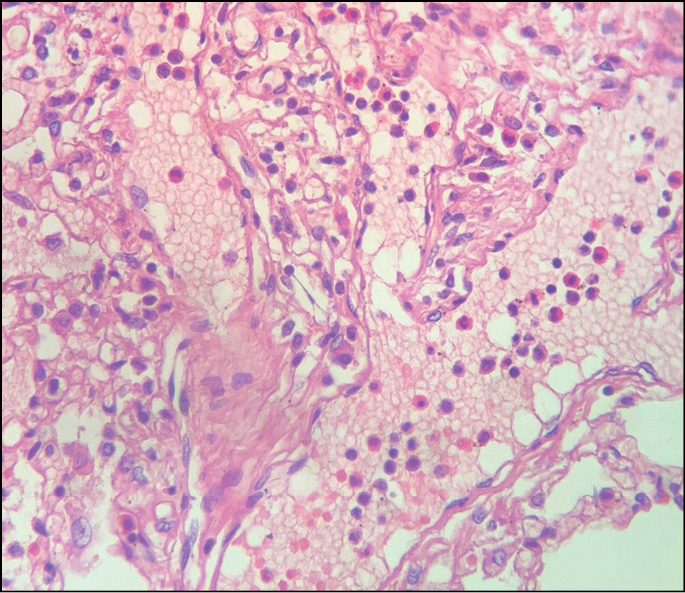

- отёк гортани, гиперплазия лимфоидных фолликулов; очаговая лимфоидная инфильтрация с эозинофильными лейкоцитами в стенке трахеи (рис. 1);

Рис. 1. Лимфоидная инфильтрация с эозинофильными лейкоцитами в стенке трахеи. Окраска гематоксилином и эозином, ×20.